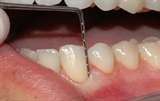

undersøkelse hos tannlegen

Tannlegen undersøker hver enkelt tann etter hull og skader.